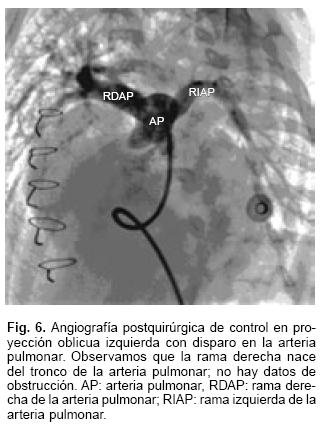

La operación consistió en el reimplante de la rama derecha de la arteria pulmonar al tronco de la arteria pulmonar; sección y sutura del conducto arterioso y dilatación de la vena pulmonar superior izquierda con un dilatador de tipo Heggar del número 8. El tiempo de circulación extracorpórea fue de 101 min y el de pinzamiento aórtico de 60 min. Tres meses después se hizo un cateterismo de control (Fig. 6). Se demostró que la RDAP estaba bien conectada y no había datos de obstrucción; la vena pulmonar se vaciaba libremente y la presión sistólica en la arteria pulmonar fue de 40 mm Hg. La función ventricular izquierda era normal con 60% de fracción de eyección.